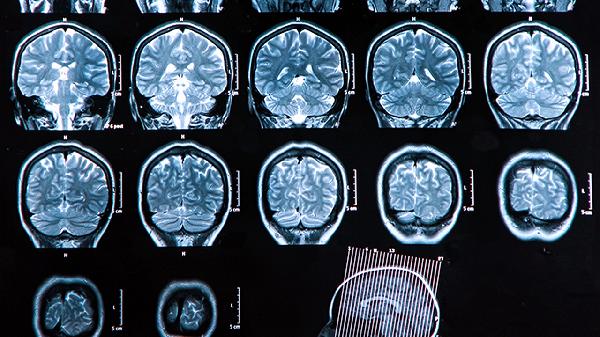

大脑前额叶发育不完全通常不建议直接使用药物干预应以行为训练和环境调整为主。若存在注意力缺陷多动障碍等明确诊断,可遵医嘱使用哌甲酯、托莫西汀、可乐定、胍法辛、舍曲林等药物辅助治疗。

前额叶发育是持续至25岁的生理过程,药物仅作为辅助手段。建议结合认知行为疗法、执行功能训练等非药物干预,保证充足睡眠和Omega-3脂肪酸摄入,避免高糖饮食影响神经可塑性。定期进行神经心理评估调整干预方案,家长需保持耐心建立结构化生活环境。